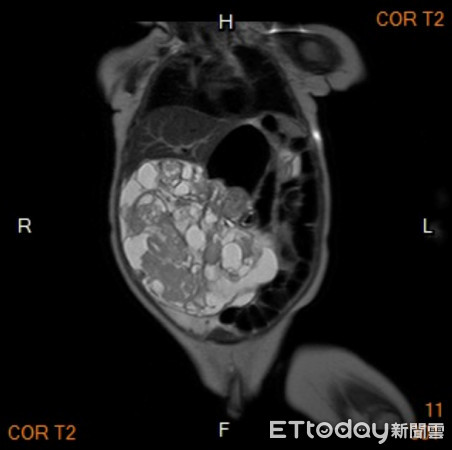

▲3月大嬰腹脹如石頭,竟是「畸胎瘤」穿透胃...跟頭一樣大!(圖/三總提供,下同)

一名3個月大的男嬰,因腹脹嘔吐及食慾不振,由母親帶至小兒科求診,腹部超音波發現有胃部前壁腫瘤,大小超過10公分,且呈現「水囊」狀,會診小兒外科做進一步評估,初步判定為畸胎瘤,安排手術切除後將腫瘤送驗,病理報告顯示為未成熟畸胎瘤,病童術後恢復良好,已於2周後順利出院。

▲男嬰腹部卡滿畸胎瘤。